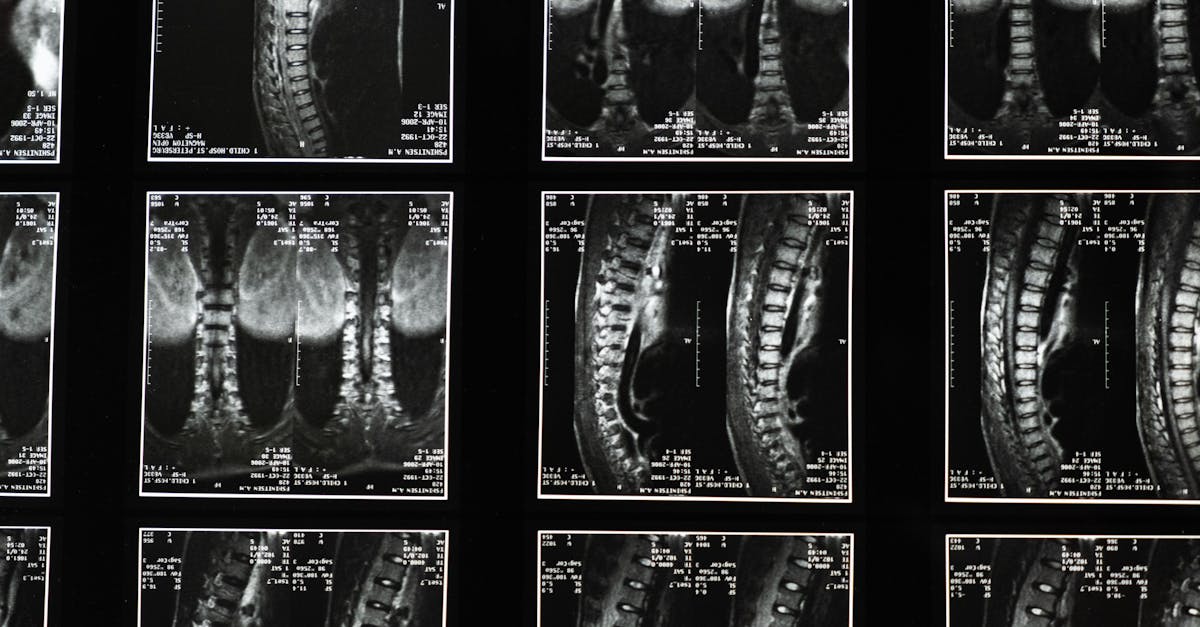

On the other hand, magnetic resonance imaging (MRI) is recognized for its exceptional image quality and lack of ionizing radiation. While MRI may be more expensive upfront compared to X-rays, its diagnostic capabilities often lead to improved patient outcomes and reduced need for follow-up imaging studies. The ability of MRI to provide detailed information about soft tissues, such as organs and joints, makes it a valuable tool for diagnosing conditions like tumors, brain disorders, and musculoskeletal injuries.

There are several types of medical imaging techniques, including X-rays, CT scans, MRI scans, ultrasound, and nuclear medicine imaging. Each technique uses different principles to create images of the body's internal structures.